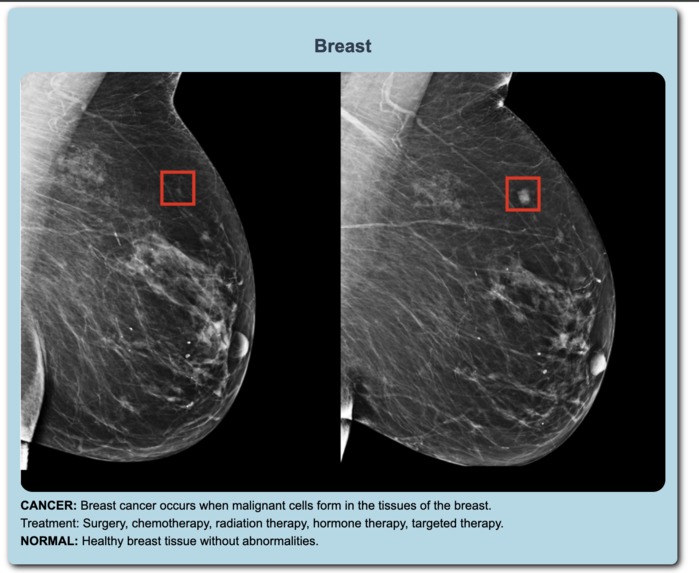

The AI-Powered MediKit enhances medical analysis with several advanced features. Most of its functionalities are classification-based, but instead of relying on conventional CNNs, we've incorporated Vision Transformers (ViTs) for model training. While CNNs and CNN-based networks like ResNet excel in detecting simple features, they struggle with the subtle details often present in medical images. Vision Transformers, however, excel at capturing these delicate features. Additionally, the MediKit offers Heartbeat Analysis using MFCC to classify heartbeats, which helps in identifying abnormalities. We also provide few-shot classification for tablets, minimizing the need for retraining the network with new data. The project includes a herbal solution feature where users can inquire about herbal remedies.

The development process involved analyzing the risk of misidentifying features in medical images, which can be critical. We compared the performance of ViTs with CNN-based networks and found that ViTs perform better for subtle features. Reference